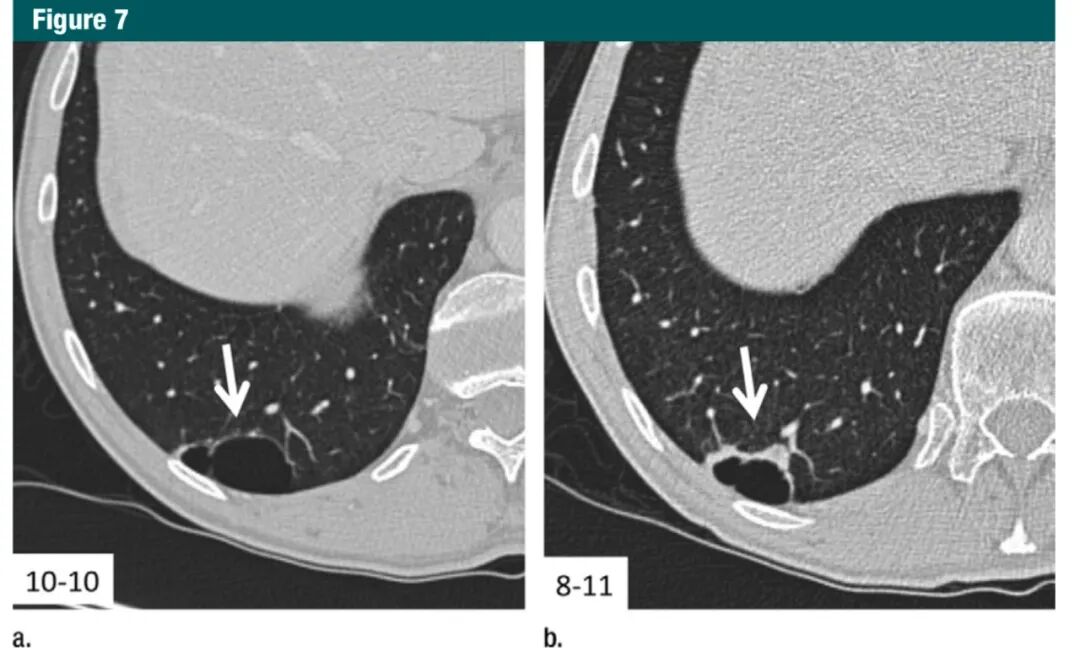

对于>8mm 的孤立实性非钙化结节,考虑3 个月后随访,作出诊断需要结合 PET 和 CT,组织取样,或选择上述方法的组合。需适当的依据大小、形态、伴随疾病和别的因素作出选择哪种方法(1A级:强烈推荐,高质量证据)。虽然 8mm 的实性结节的平均患癌风险仅仅为约3%,具体依赖于形态和位置,但在某些特定患者中,风险可以明显高于该百分比。当结节增大、它们的形态变得更加清楚,对其处理策略依据结节的表现较大小更为重要(图5-7)。因此,本指南包括了有创和无创的处理选择。

图7:横断面1mmCT层面,相隔10个月前后对比,右下肺囊状病灶囊壁进行性增厚,高度怀疑恶性(箭头)。术后病理为浸润性腺癌7Gc帝国网站管理系统